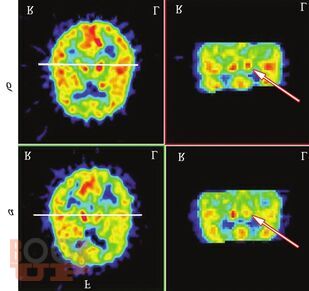

В книгу включены данные о собственных наблюдениях автора за естественным течением ЦВЗ на протяжении 2—5 лет после определения регионарной перфузии церебральных зон методом позитронно-эмиссионной томографии. Выявлены те церебральные зоны, поражение которых имеет особенно неблагоприятный прогноз.